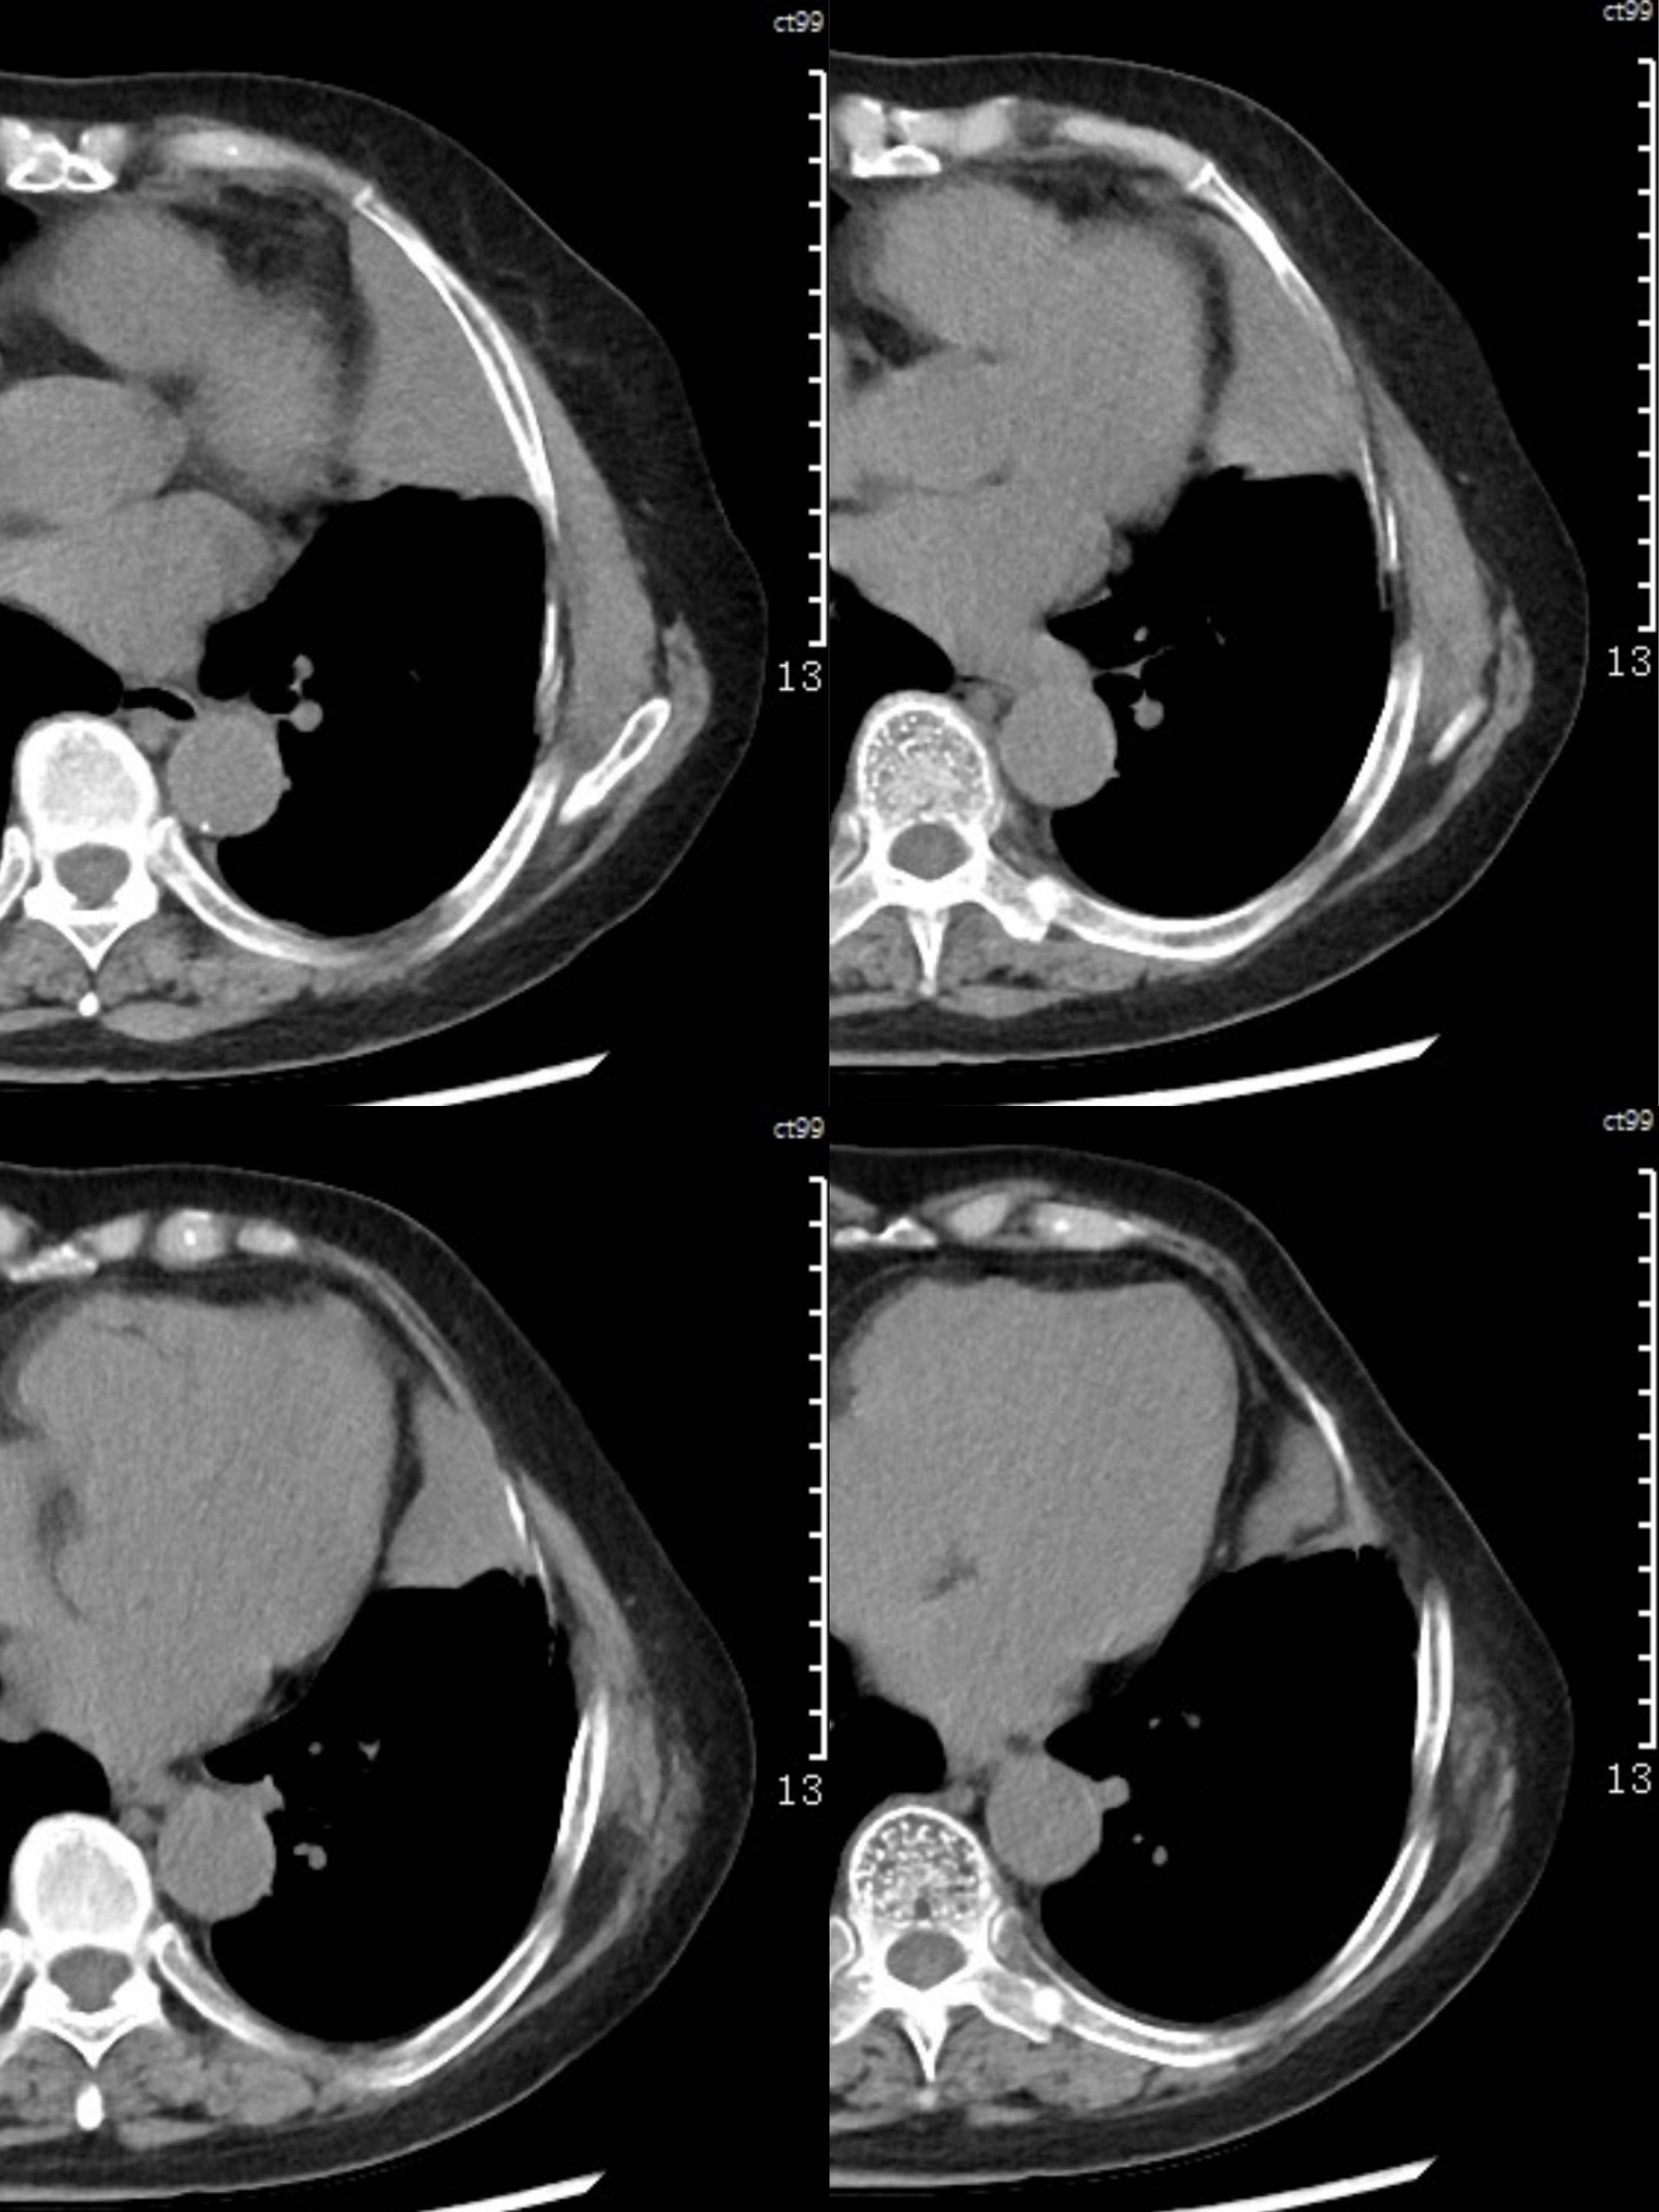

女73岁,体检发现左上纵隔占位1周

患者于1周前体检行CT检查提示:“左上纵隔见不规则团块状软组织密度影,大小约90*63mm”,患者平素偶有头晕,无明显胸闷气急,今为进一步治疗来我院就诊, 门诊以"左上纵隔肿物"收入院。

糖类抗原125(CA125):44.9(正常0-30.2),余实验室检查无殊